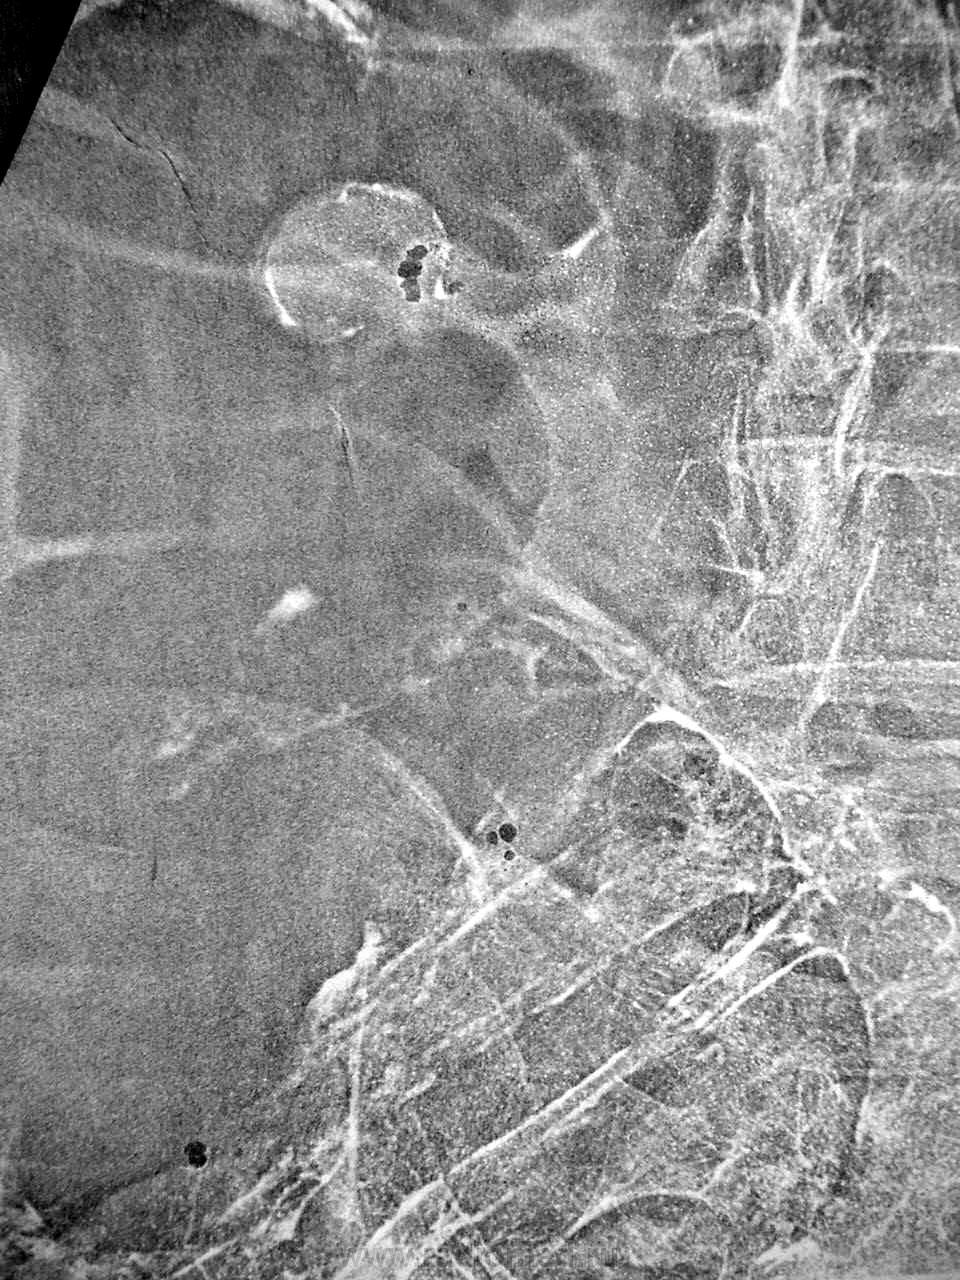

Это выше баугиниевой около 8 см., и к ней не относится...

При операции - новообразование по типу большого неправильной формы полипа, гистология - неходжкинская лимфосаркома...